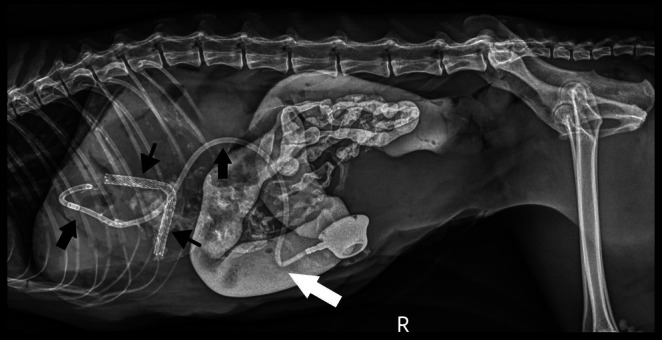

Post‐operative radiographs confirmed appropriate placement of the stent and the biliary drainage catheter (Figure 2). Abdominal ultrasonography showed asymmetric biliary tract decompression, with persistent right‐sided intrahepatic biliary tract dilatation (Figure 3A) and resolved left intrahepatic biliary tract dilatation (Figure 3B). The stent was visualized extending from the duodenal lumen through the CBD and into the left lateral liver lobe within the biliary tract (Figure 3C). A large volume of echogenic peritoneal effusion also was observed with hyperechoic mesenteric fat. Fluid analysis was consistent with mild mixed inflammation; no bacteria were seen; aerobic and anaerobic cultures were negative.

Improvement of hyperbilirubinemia and increased liver enzyme activities was noted post‐operatively (Table S1). Post‐operative radiographs showed an appropriately‐placed stent and biliary drainage tube (see Figure 5). A partial kink of the tubing was seen as it entered the body wall, but it was of no clinical consequence. Ultrasonography showed asymmetrical decompression of the intrahepatic biliary duct tracts, with ongoing right biliary obstruction and left‐sided decompression (Figure 6). Echogenic peritoneal effusion and hyperechogenicity of the cranial mesenteric fat also were noted.